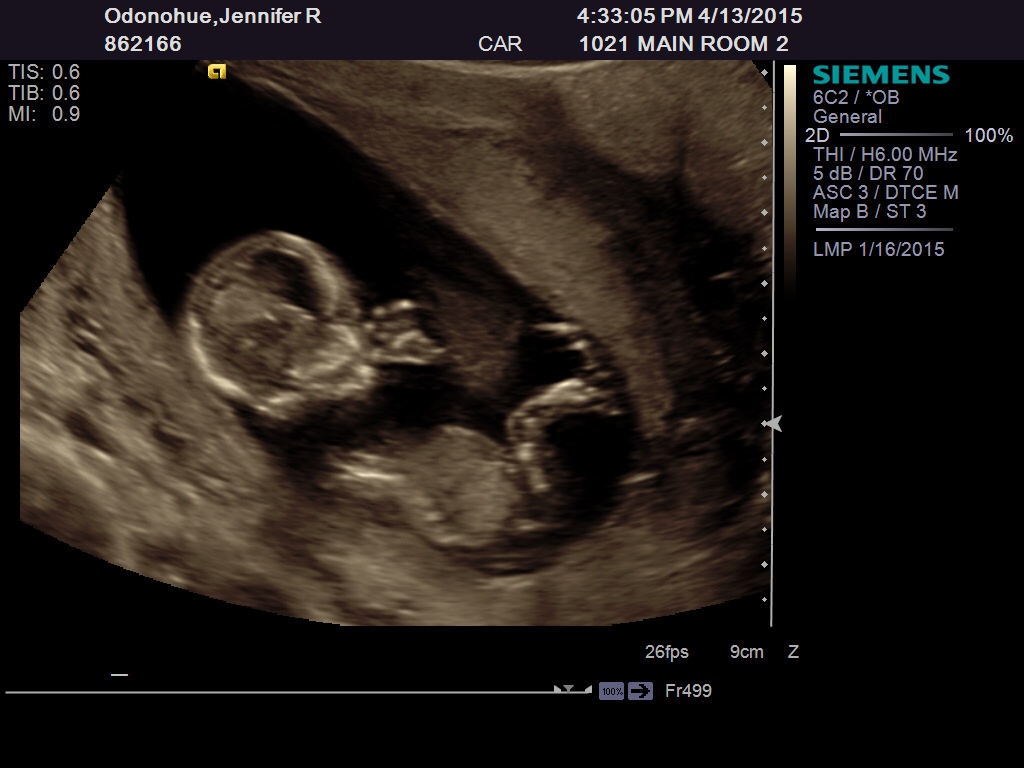

ooh. that is a good one. When I rotate it the nub seems to be high angled but its also looking clean split. Boy looking skull though Good luck!

*possibly* boy

Maaaaybe boy :)

Maybe boy? Not real confident though. Could be girl looking at the second pic. 50/50 split from me!

Girl :)